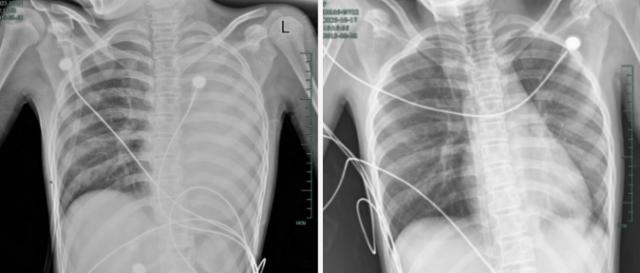

发热仅1天,肺全白了!这种病极度危险,千万别当普通感冒

孩子感冒咳嗽看似常见,可12岁女孩笑笑(化名)的经历却让人感到后怕——仅发热1天,左肺就变成了“白肺”,呼吸急促到无法平躺,血氧饱和度勉强维持在90%左右,情况十分危急!